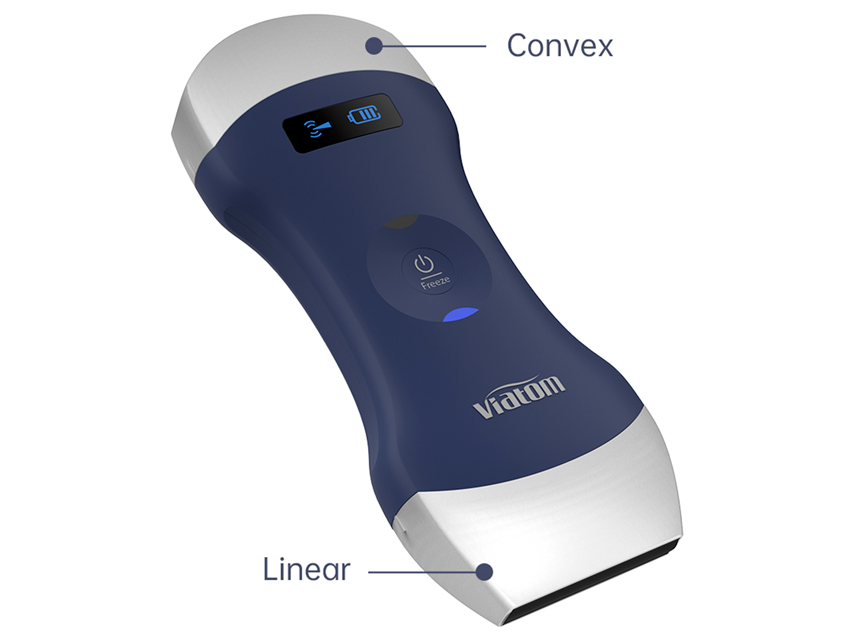

PORTABLE LINEAR/CONVEX DOUBLE HEAD WIRELESS ECOGRAPH VIATOM available December 2023

WIRELESS PORTABLE ULTRASOUND SCANNERS

Dual-head ultrasound

Linear head and convex head interchangeable by simply turning the device.

All models have GB, IT manual. Probe type: Linear / Convex

Frequency range: 7.5-10 MHz / 3.5-5 MHz

Scanning depth: 20/40/60/100 mm / 90/160/220/305 mm

Head width: 40 mm / 45 mm